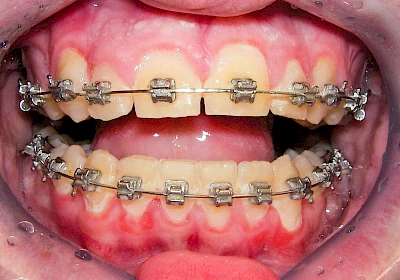

Bakterien in den Zahnbelägen greifen neben den Zähnen auch das Zahnfleisch (Gingiva) und den gesamten Zahnhalteapparat (Parodont) an. Der Körper reagiert mit einer Entzündung, sichtbar als Rötung und Schwellung. Meist blutet das Zahnfleisch z .B. beim Essen oder auch beim Putzen der Zähne.

Ist zunächst nur das Zahnfleisch von der Entzündung betroffen, spricht man von Gingivitis. Später, wenn auch der Knochen um die Zähne herum entzündet ist, spricht man von einer Parodontitis. Bei der Parodontitis wird der Knochen nach und nach abgebaut und das Zahnfleisch zieht sich zurück. Die Zahnhälse und Zahnwurzeloberflächen liegen mehr und mehr frei. Die Zähne werden zunehmend lockerer und fallen schließlich aus.